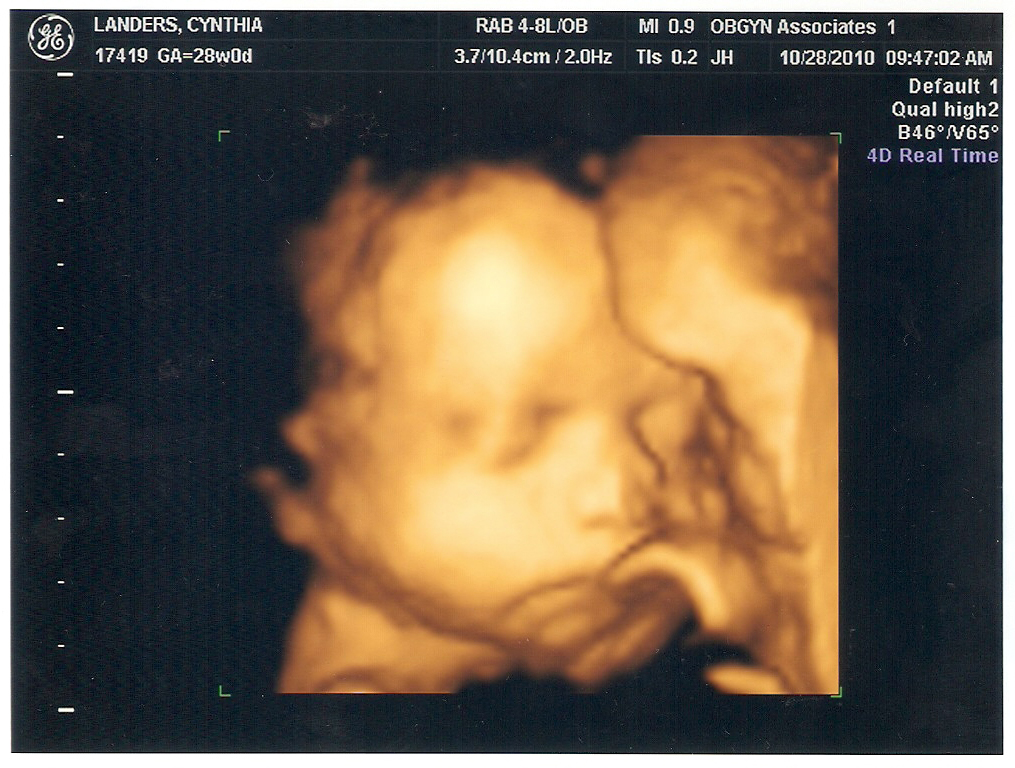

During my ultrasound this past Thursday, Julie noticed that my placenta is low lying (but not over my cervix). Dr. W. said I shouldn't make any major changes in my routine for now, but he'll really be looking out for Parker and I both as we get closer to his due date. His goal for now is to get us through eight more weeks safe and sound, and then take each day from there one at a time.